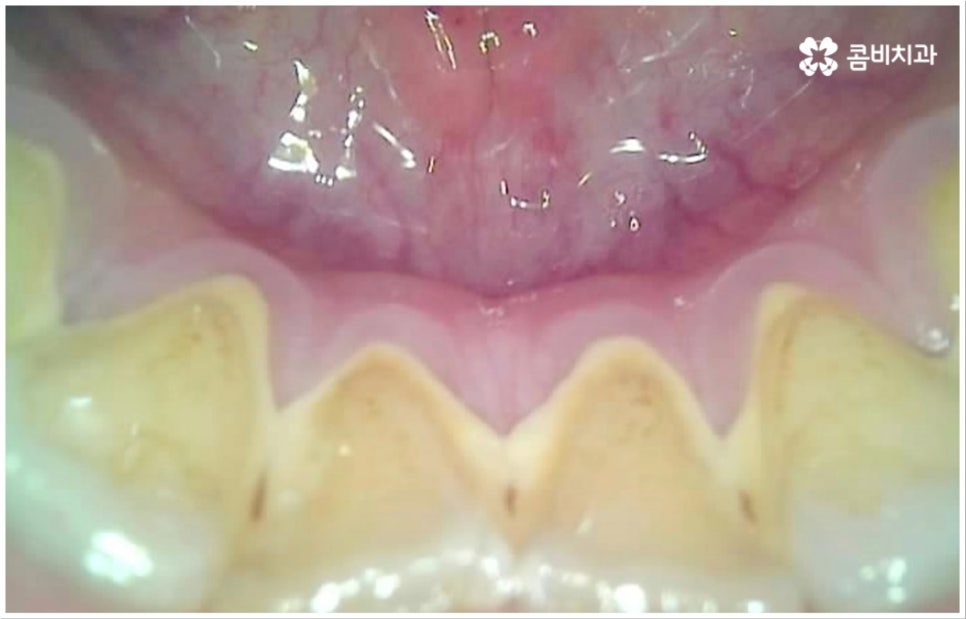

많은 분들이 살면서 한 번쯤 앓아봤을 충치는 이와 같은 교합면에만 발생하는 것이 아니라 치아와 치아 사이 인접면에 발생할 수도 있는데요. 인접면 충치는 치아끼리 맞닿은 좁은 틈새에 음식물 찌꺼기가 잘 끼고 또한 이것이 양치질을 통해서도 쉽게 빠지지 않아 관리가 어렵기 때문에 생기는 경우가 많은데, 교합면 충치에 비해 발견과 치료가 어려운 편이라고 할 수 있어요.

물론 앞니 등 노출이 되는 부위의 인접면 충치는 비교적 쉽게 알아차릴 수 있고 치료를 위한 접근 역시 용이한 편이나 어금니 인접면 충치 같은 경우 바로 드러나는 부위가 아니므로 육안으로 식별이 잘 되지 않고 엑스레이를 찍어도 초기에는 확인이 어려워 어느 정도 병증이 진행된 후 발견하게 되는 경우가 종종 있는데요. 치아의 인접면은 교합면에 비해 상대적으로 법랑질이 얇기 때문에 상아질 안 쪽 치수 신경까지 세균이 침투하는 속도가 빨라서 자칫 치료 시기를 놓치면 충치 통증 이 많이 심해지고 신경 치료까지 진행해야 하는 상황까지 발생할 수 있으니 조심하실 필요가 있습니다.